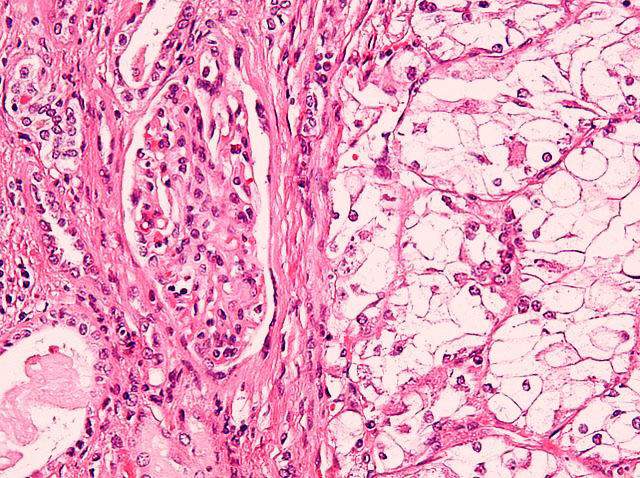

Njurcancer är svårt att upptäcka

Cancer, Unga intervjuar forskare 2014-12-03

Njurcancer är en allvarlig sjukdom som drabbar ungefär tusen personer varje år. Symptomen är ofta väldigt svåra att upptäcka i tid och njurcancer är därför en väldigt svår sjukdom att bota. Ungefär 40 procent av de nyupptäckta fallen har redan hunnit sprida sig till andra organ i kroppen, oftast hjärnan, lungorna, skelettet med mera. Vi besökte Martin Johansson, forskare inom patologi med inriktning på njurarna, som berättade om arbetet på patologen i Malmö. Läs mer > >